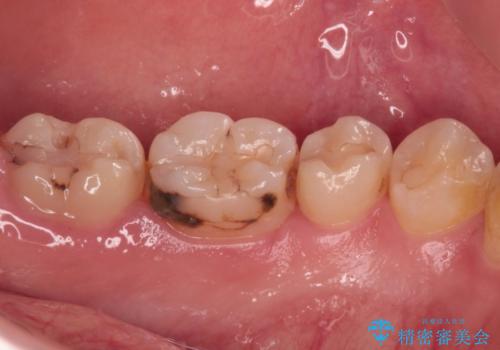

- 奥歯の歯肉から定期的に膿が出てくるとのことで来院された患者様です。

レントゲン写真などの診察を行った結果、根管治療が必要であったため、現在のクラウンを除去し、根管治療を行うこととしました。

根管治療後は症状を確認し、速やかにオールセラミッククラウンにて補綴治療を行うこととしました。